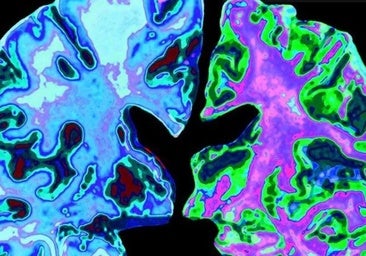

Investigadores de la Escuela de Medicina de Harvard, en Estados Unidos, han descubierto que la pérdida de litio en el cerebro acelera el deterioro de la memoria, contribuyendo a la enfermedad de Alzheimer, y han abierto la posibilidad de que este compuesto ayude al tratamiento de una patología que afecta a cerca de 400 millones de personas en el mundo.

El alzheimer implica una serie de anomalías cerebrales, como acumulaciones de la proteína beta amiloide, ovillos neurofibrilares de la proteína tau y la pérdida de una proteína protectora llamada REST. Sin embargo, estas no explican al completo la aparición de la enfermedad, ya que algunas personas que las presentan no muestran signos de deterioro cognitivo, además de fármacos dirigidos a la beta amiloide no logran revertir la pérdida de memoria.

El trabajo publicado en 'Nature', y elaborado a lo largo de 10 años, desvela que el litio podría ser la clave para completar la historia en torno al Alzheimer. Según demuestra por primera vez, el litio se produce de forma natural en el cerebro, lo protege de la neurodegeneración y mantiene la función normal de todos los tipos principales de neuronas.

El litio fue el único metal cuyos niveles fueron notablemente diferentes entre los grupos y que se alteró en las primeras etapas de la pérdida de memoria. Sus niveles fueron elevados en los donantes cognitivamente sanos, pero muy reducidos en aquellos con deterioro leve o alzheimer avanzado. Estos hallazgos fueron replicados en muestras obtenidas de múltiples bancos de cerebros de todo el país.